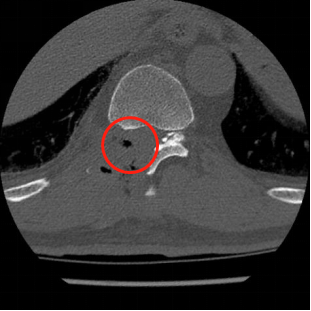

术前MRI影像提示胸椎黄韧带肥厚,胸段脊髓信号改变。

术前术后CT影像资料